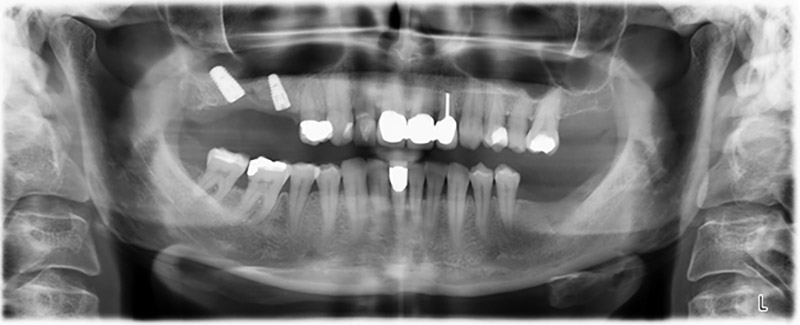

La paziente, 59 anni, presenta un caso di parodontite avanzata e descrive una sensazione di fastidio e scarsa sensibilità gustativa dal primo quadrante in direzione distale. L'esame clinico rivela tasche parodontali generalmente diffuse e un'atrofia ossea molto avanzata nelle regioni 16 e 14. L'esito è confermato dalla radiologia (fig. 1). Non è possibile salvare i denti 16 e 14.

Al fine di pianificare e minimizzare i rischi, circa sei mesi dopo l'estrazione dei denti 16 e 14 viene effettuata una tomografia digitale volumetrica (DVT, Planmeca), la quale conferma chiaramente la mancata rigenerazione ossea nel volume desiderato (da fig. 2 a 7).